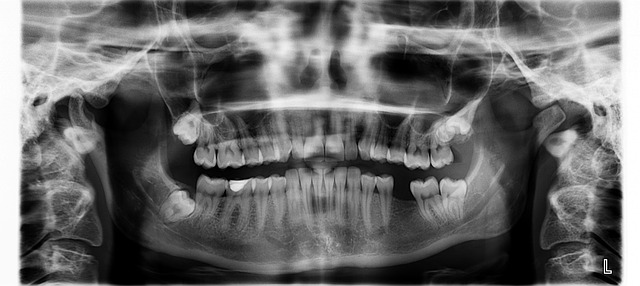

임플란트 시술은 가격 편차가 심한 시술 중 하나입니다. 다른 시술도 마찬가지지만 어떠한 의료인이 시술하고 재료의 가격에 따라서 비용이 달라지게 됩니다. 하지만 같은 병원에서 같은 재료를 사용하더라도 비용의 차이가 발생할 수 있는데 그 이유는 시술받는 환자마다 구강상태가 다르기 때문에 비용적인 차이가 발생하게 됩니다.